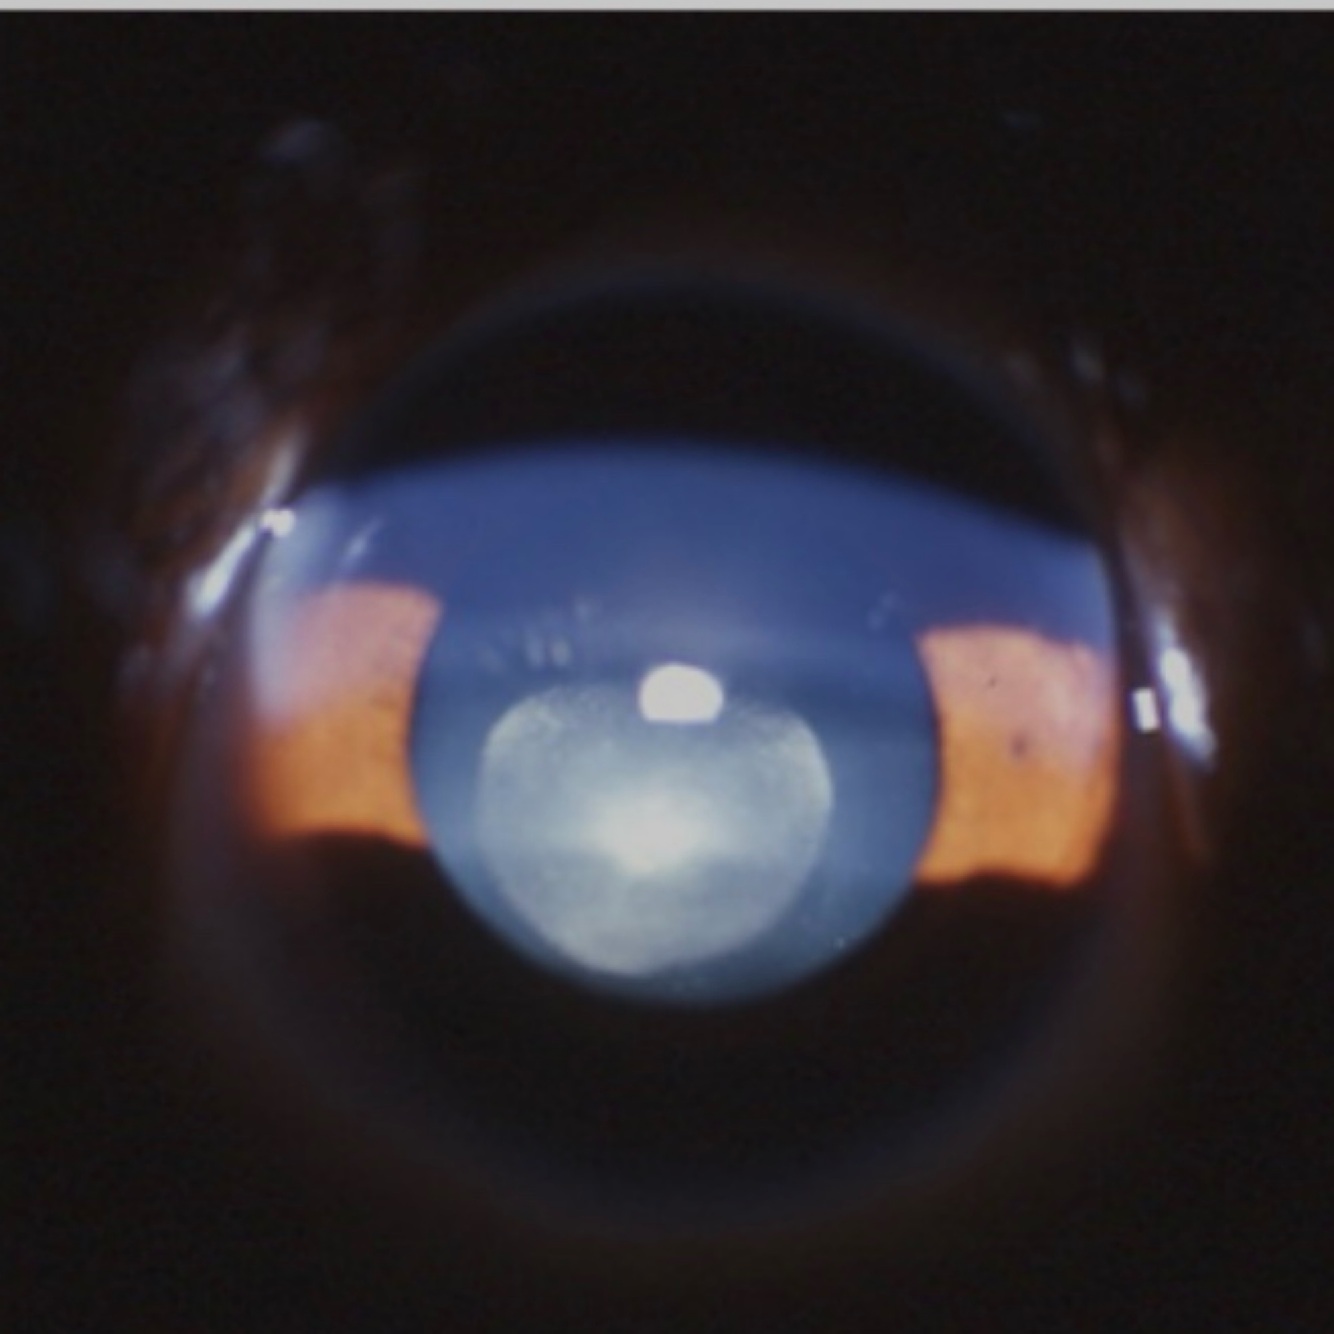

Congenital zonular cataract